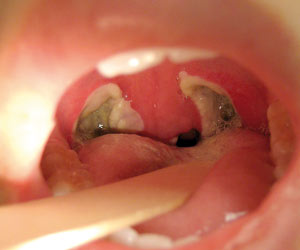

يُعد التهاب اللوزتين التهابًا يصيب اللوزتين، وهما جزآن لينان بيضاويا الشكل من الأنسجة والتي توجد في نهاية الحلق حيث توجد لوزة في كل جانب. ما هي اعراض التهاب اللوزتين عند الاطفال؟ تتشكل أنسجة بيضاء الشكل في مؤخرة الحلق عند إصابة الطفل بإلتهاب اللوزتين بسبب دخول جراثيم أو ميكروبات إلى الجسم عن طريق الفم. ان تضخم اللوز في بعض الاحيان بشكل كبير مع وجود الالتهاب او بدونه قد يسبب الشخير عند الاطفال، فاذا حدثت حالات اختناق جراء تضخم اللوز واستدعت الضرورة فيمكن ازالتها عند عمر ستة شهور، ومن طرق ازالتها يتمثل العلاج في مراجعة الطبيب المختص ليعطي الطفل الدواء اللازم كالمضادات الحيويّة التي تُخفف شدة الالتهاب والتضخم، إلى جانب الأخذ بالعادات الصحيّة السليمة أثناء فترة العلاج كالنوم والراحة، وشرب كميّة كافية من السوائل. تظهر بعض الأعراض على الطفل بعد التعرض لتضخم اللوز ومنها

حصى اللوزتين ويكيبيديا

حصى اللوزتين ويكيبيديا from upload.wikimedia.org

ملاحظة التهاب اللوزتين باستخدام خافض اللسان وملاحظة تكون تقيحات. تتم معالجتها حالياً بجرعة واحدة من الستيروئيدات عند كل التهاب. وجع الحلق، وقيل دم يهيج في حلق الإنسان، وتتأذى منه اللحمتان اللتان. التهاب اللوزتين هو مرض من الأمراض الشائعة والمنتشرة بشكل كبير وخصوصا عند الأطفال. يسبب التهاب الأذن الوسطى آلاما كبيرة عند الأطفال. • ما هي أسباب انسداد الأنف عند الأطفال: انسداد الأنف المزمن والذي يؤثر على نوم الطفل غالبا ما يكون بسبب تضخم اللحمية البلعومية وقد يصاحبه تضخم في اللوزتين ايضاً. يُساهم تضخم اللوزتين في حدوث تضيّق في المسالك الهوائية، مما يزيد من فرص الإصابة بالشخير وانقطاع النفس أثناء النوم. إيقاف التهاب اللوزتين قبل حدوثه. أسباب تضخم اللوزتين عند الأطفال. .اللوزتين عند الاطفال عمر سنتين بالاعشاب وصفة فعاله لعلاج تضخم والتهاب اللوزتين عند الاطفال بمكون واحد من مطبخك كيف نمنع مع الدكتور الفايد بخصوص النظام الغذائي للطفل التهاب اللوزتين عند الأطفال. أهم المعلومات عن التهاب اللوزتين. التهاب اللوزتين عند الاطفال يصاحبه تضخم الناميات الانفية او ما يسمي باللحمية ، والتي هي ايضا تتكون من نسيج ليمفاوي شبيه بنسيج اللوزتين ، وتضخمها سيحدث ضغطا علي الفتحتين السفليتين لقناة استاكيوس وربما انغلاقهما ، والذي سيؤدي حتميا الي تجمع.